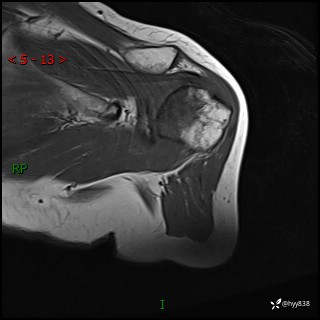

肱骨MRI平扫(axi T1WI+cor T2WI-fs)+CE-fs(COR+SAG)